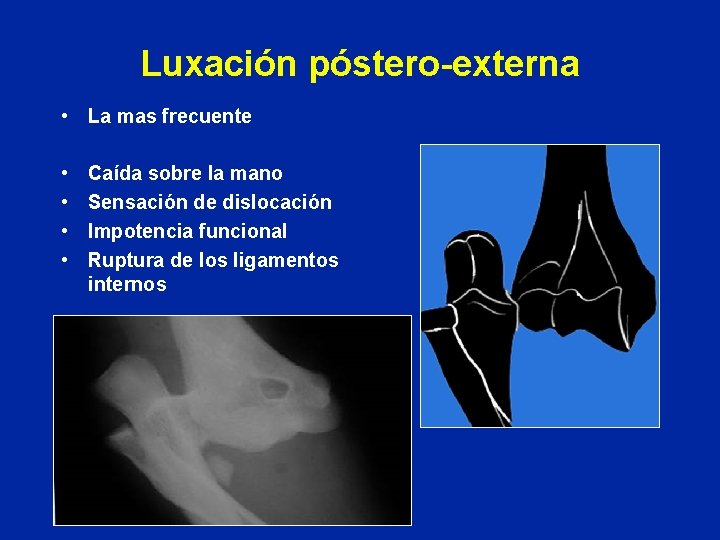

Luxación póstero-externa • La mas frecuente • • Caída sobre la mano Sensación de dislocación Impotencia funcional Ruptura de los ligamentos internos